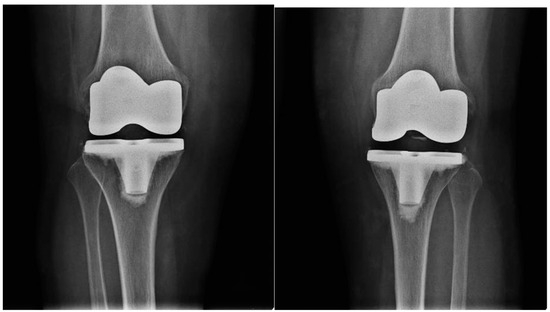

All patients had an indication for bilateral surgical treatment from the outset, with a Kellgren–Lawrence score of 3 or 4 (Figure 1), without previous knee replacement surgeries. Patients with unicompartmental knee replacements, complicated prostheses, secondary arthritis due to systemic or post-traumatic disorders, and with coagulation disorders were excluded.

Figure 1. Severe bilateral osteoarthritis of the knee.

The knee is the joint most affected by osteoarthritis, accounting for almost four-fifths of patients worldwide [1]. Osteoarthritis is a chronic irreversible condition that progressively becomes resistant to conservative treatments, such as pharmacotherapy and physiotherapy. Joint replacement surgery remains the only definitive approach to control symptoms and improve patient’s quality of life [2]. Today, total knee arthroplasty (TKA) is a routine procedure in orthopedic surgery to restore function in cases of severe osteoarthritis or systemic diseases. Diagnosis is mainly radiographic. The stage of knee osteoarthritis can be determined through one of the most widely used radiographic classifications: the Kellgren–Lawrence classification, which describes osteoarthritic joints in four stages of severity based on morphostructural changes [3].